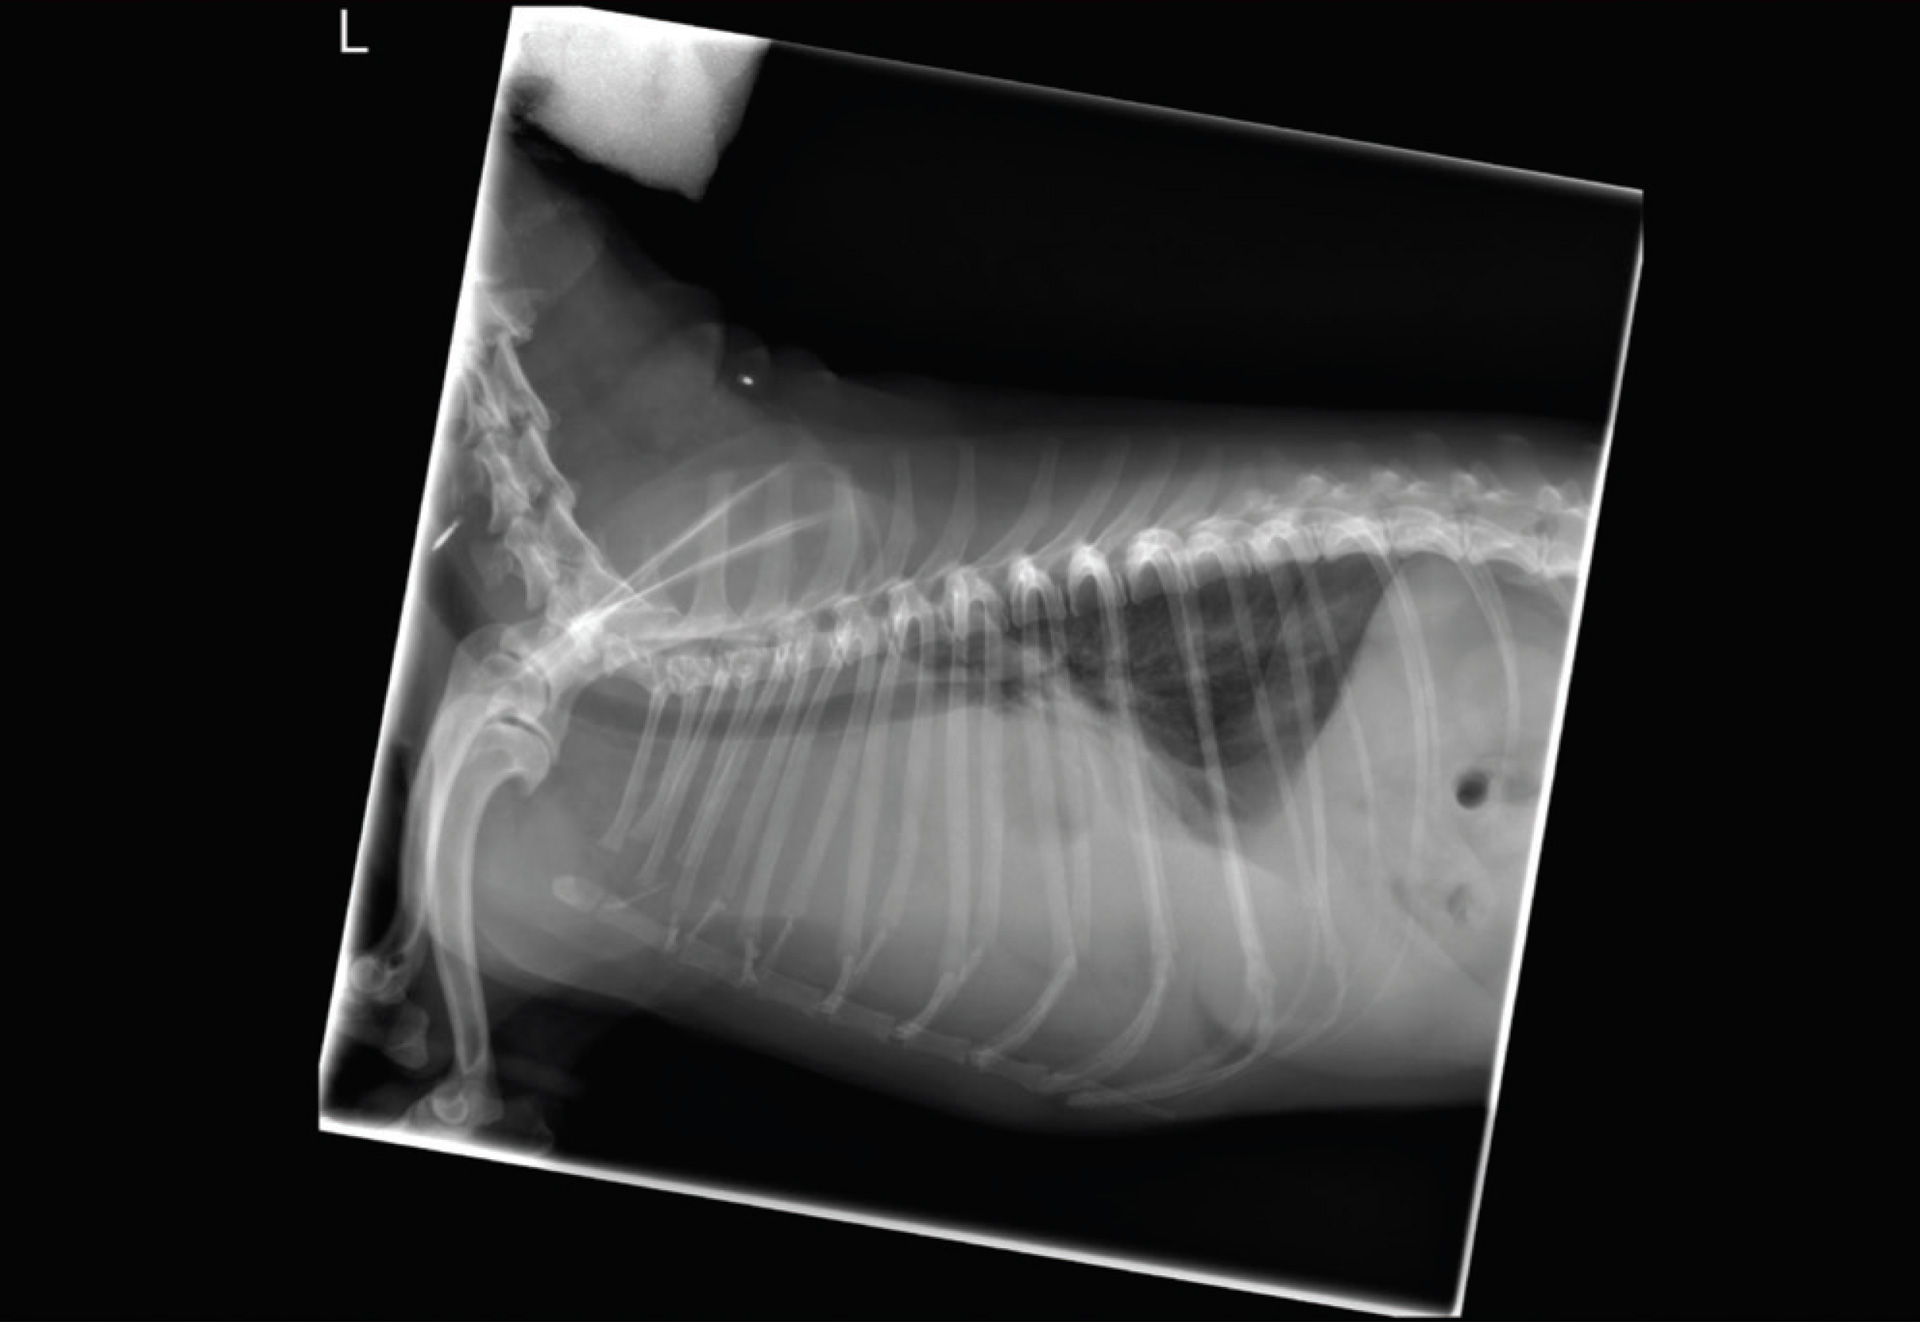

Thoracic radiographs need to be three-view. The most common areas to find lymphoma in the thorax involves the lymph nodes (e.g., sternal), mediastinum, or interstitial lung. In addition, thoracic radiographs also allow the veterinarian to evaluate for any other abnormalities which may affect the treatment plan (eg., cardiac disease). Abdominal ultrasound is preferred as it is superior to abdominal radiographs in identifying a mass, enlarged lymph nodes, intestinal wall thickening, and masses in the spleen and/or liver. Abdominal ultrasound also allows us to evaluate other organs and assess the patient’s overall health.